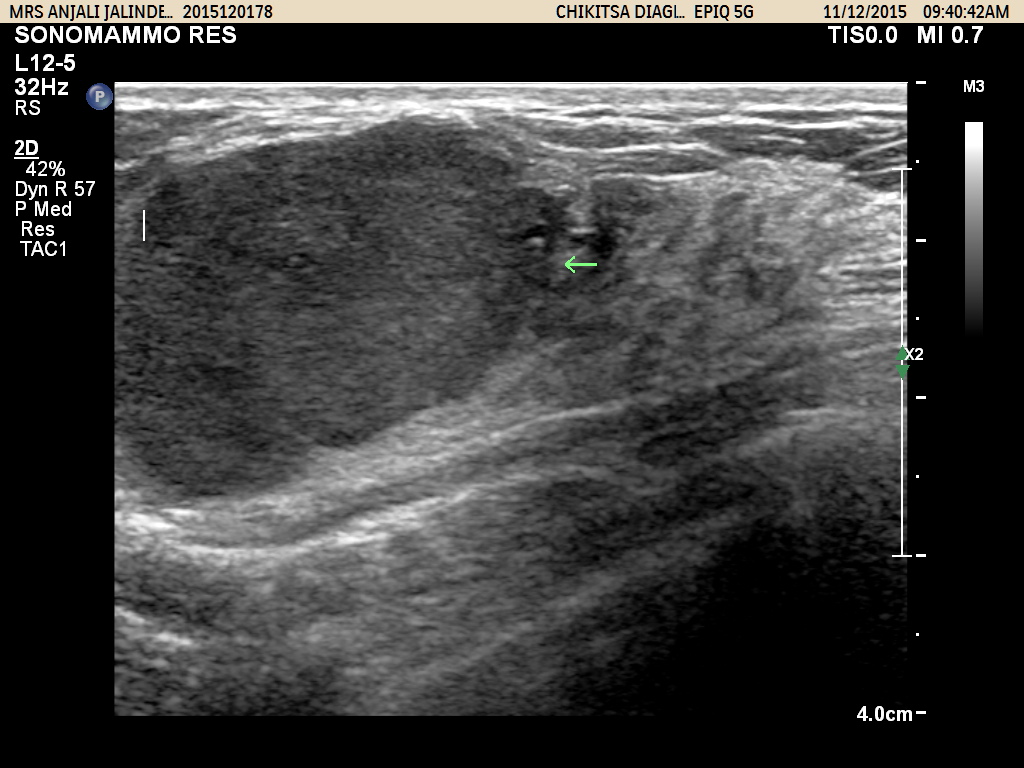

Breast Sonography (Sonomammography)

Breast ultrasound is used to help diagnose breast abnormalities detected during a physical examination (such as a lump or nipple discharge) and to characterize further findings or abnormalities seen on Xray mammography.

During ultrasound imaging of the breast Doppler techniques to evaluate blood flow may often be necessary.